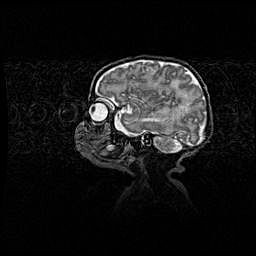

Подострая гематома правой гемисферы мозжечка.

Наружная гидроцефалия.

Возраст: 15 дней

Вес: 3100 г

Пол: женский

Окружность головы: 37 см

Срок гестации: 35-36 недель

При открытой наружной форме гидроцефалии у новорожденных расширяются и переполняются субарахноидные пространства.

Кровоизлияния в мозжечок имеют две клинико-анатомические формы: полушарные гематомы и кровоизлияния в червь.

К появлению этой патологии может привести: повреждения головного мозга, возникающие в результате асфиксии и гипоксии плода при беременности, или травмы во время родов. Редко гематома мозжечка может быть результатом первичной коагулопатии и сосудистой мальформации, диссеминированном внутрисосудистом свертывании, изоиммунной тромбоцитопении.